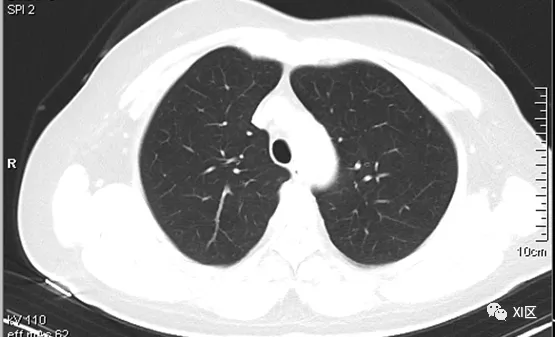

图片源自网络 图文无关